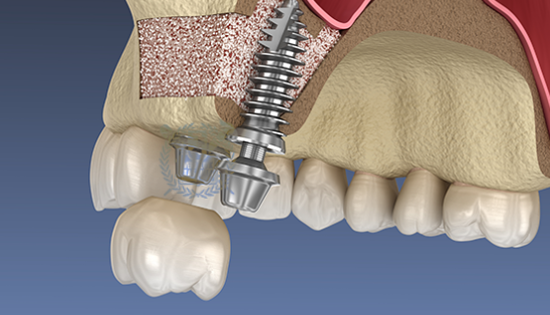

뼈이식 / 임플란트 식립공간 확보

잇몸을 절개하고 난 후 뼈를 넣고 상악동을 들어 올릴만한 작은 통로를 만들어 뼈이식할 공간과 임플란트 식립할 공간을 확보합니다.

• 03

잇몸 뼈이식 시술 진행

들어올린 빈 공간에 뼈를 이식하는데 이때 사용되는 뼈이식 재로로는 자가치아뼈, 자가골, 인공뼈, 합성골 등이 있습니다.

• 04

임플란트 매식체 식립

잔존하고 있는 잇몸뼈의 양에 따라 뼈이식과 동시에 임플란트 식립하기도 하고 6-9개월 후 식립하기도 합니다.